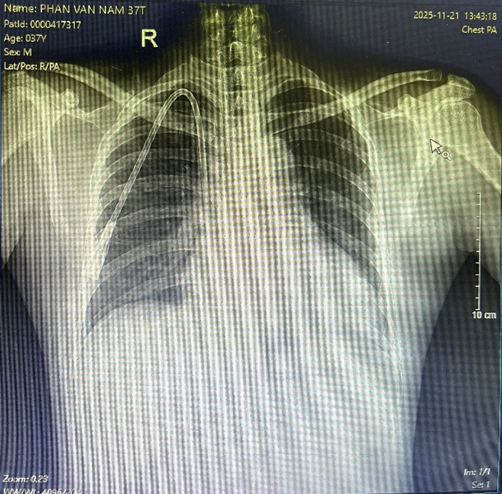

Hình ảnh: Chụp Xquang sau khi đặt catheter để kiểm tra vị trí

+ Hệ thống máy siêu âm và máy X-quang tăng sáng hiện đại, hỗ trợ định vị chính xác vị trí đặt catheter.